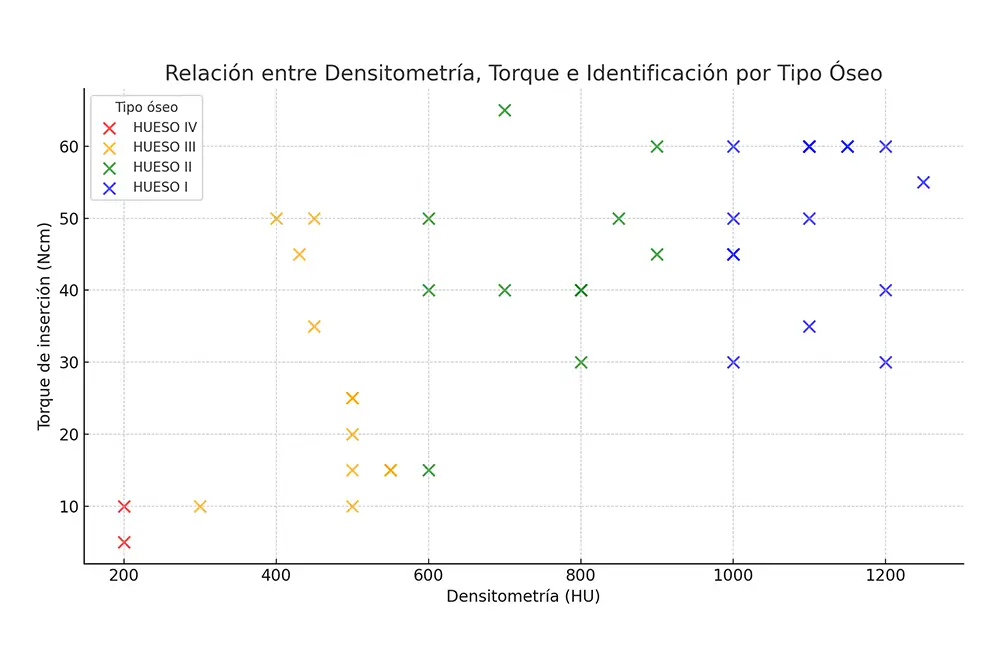

El tipo óseo más frecuente en las zonas de inserción de los implantes fue el tipo I en el 39% de los casos, siendo la media de densidad para todo el grupo de 778,78 Hu (+/- 308,56). El torque medio de inserción del grupo fue de 39,15 Ncm (+/- 17,56). La distribución de los implantes en función del torque alcanzado durante su inserción y su tipo óseo y densidad exacta se muestran en la figura 3. En ninguno de los casos incluidos en el estudio se realizaron técnicas regenerativas previas ni simultáneas a la colocación de los implantes. Sin embargo, en el 36,6% de los casos se llevó a cabo una sobrecorrección vestibular mediante la aplicación de hueso autólogo obtenido durante el fresado quirúrgico y embebido en PRGF-Endoret. No se registraron fracasos implantológicos durante el periodo de seguimiento, el cual tuvo una media de 20,90 ± 6,04 meses tras la carga funcional, lo que se traduce en una tasa de supervivencia acumulada del 100%. Todas las prótesis realizadas fueron atornilladas mediante transepitelial, siendo la supervivencia de las mismas del 100%. Unicamente se registraron 2 eventos de aflojamiento de tornillos durante el período de seguimiento.

Figura 3. Torque final de inserción de cada uno de los implantes y densidad ósea del lecho, categorizado en función del tipo óseo.